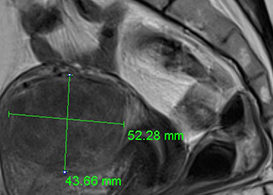

고해상도 MRI 영상

Precise Positioning환자의 체형과 굴곡, 자궁과 종양의 위치와 크기에 맞춰 고강도 집속

초음파 에너지 진입경로를 정확하게 설정합니다.